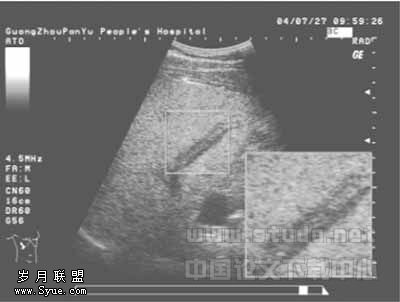

华支睾吸虫及其分泌物致胆道阻塞5例,其中累及肝右前叶2例,整个肝右叶1例,胆总管2例。超声表现为胆管较均匀扩张、管壁增厚,呈低回声,与周围肝组织界限清晰,胆管内充满不均质回声,见图4。

图4 肝吸虫致胆道阻塞,胆管扩张,管壁增厚,呈低回声,管腔内充满不均质回声